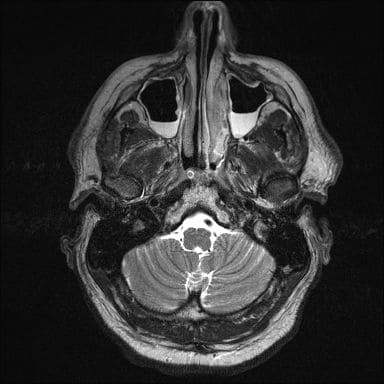

МРТ головного мозга. В указанную стоимость входит проведение сканирования, описание результатов исследования на фирменном бланке, выдача результатов МРТ в полном объёме на компакт диске (CD) или в виде жёсткой копии на плёнке. При желании вы можете заказать большее количество носителей.

МРТ придаточных пазух носа позволяет выявить различные патологии гайморовых, лобных пазух, которые анатомически находятся около носа. Они представляют из себя специфические полости, которые согревают и увлажняют вдыхаемый воздух.

МРТ околоносовых пазух назначается при головных боля неясной этиологии, особенно сопровождаемых отделением слизи из носа, частых кровотечениях и других патологических состояниях. Это наиболее точный метод диагностики, который показан на последнем этапе, в случае, когда другие исследования не выявили отклонения.